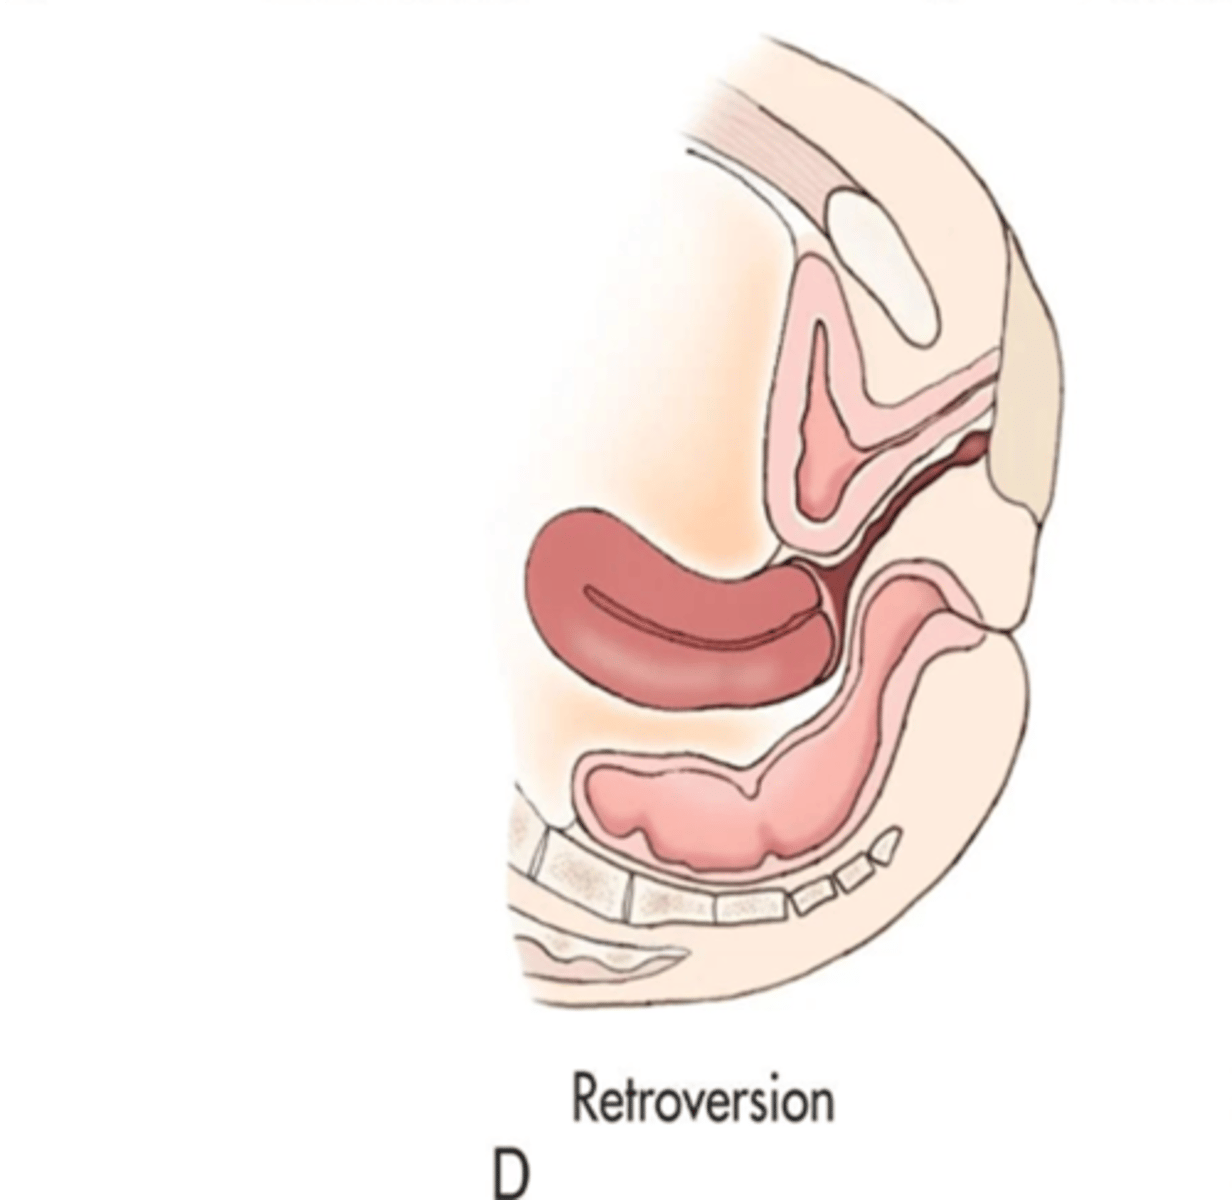

What is a retroverted uterus?

fundus and body tilts backward, fundus and vagina are aligned

A retroverted uterus is common with ___

multiparity